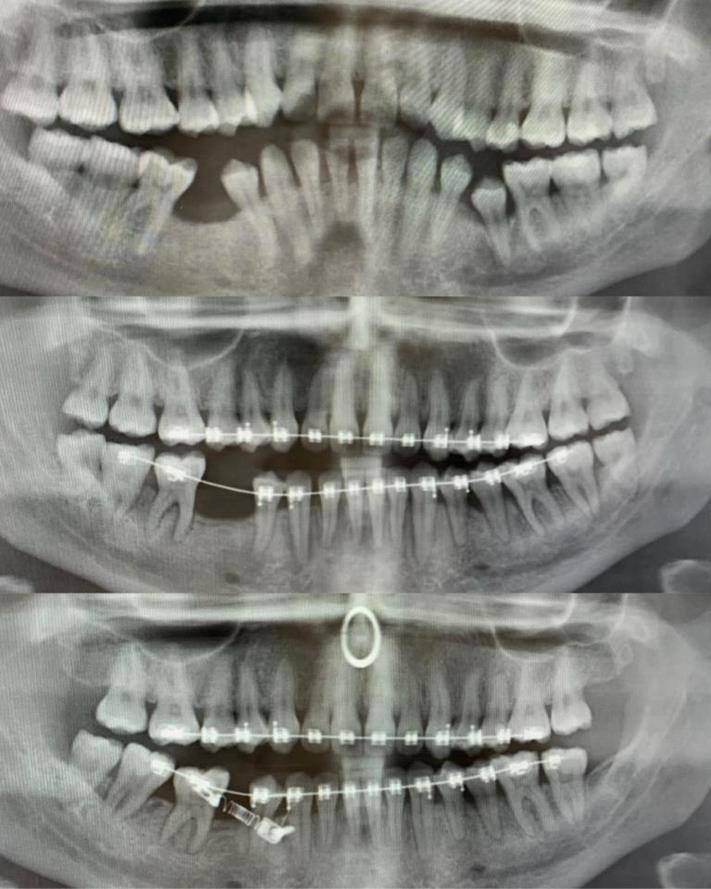

Երեխայի ծնոտը, որի մեջ «թաքնված» են դեռ չծակած սեղանատամները

Եվ ահա, թե ինչպես է հիմնական ատամը «ճնշում» կաթնայինին` զբաղեցնելով նրա տեղը

Ահա, թե ինչպես են աշխատում բրեկետները